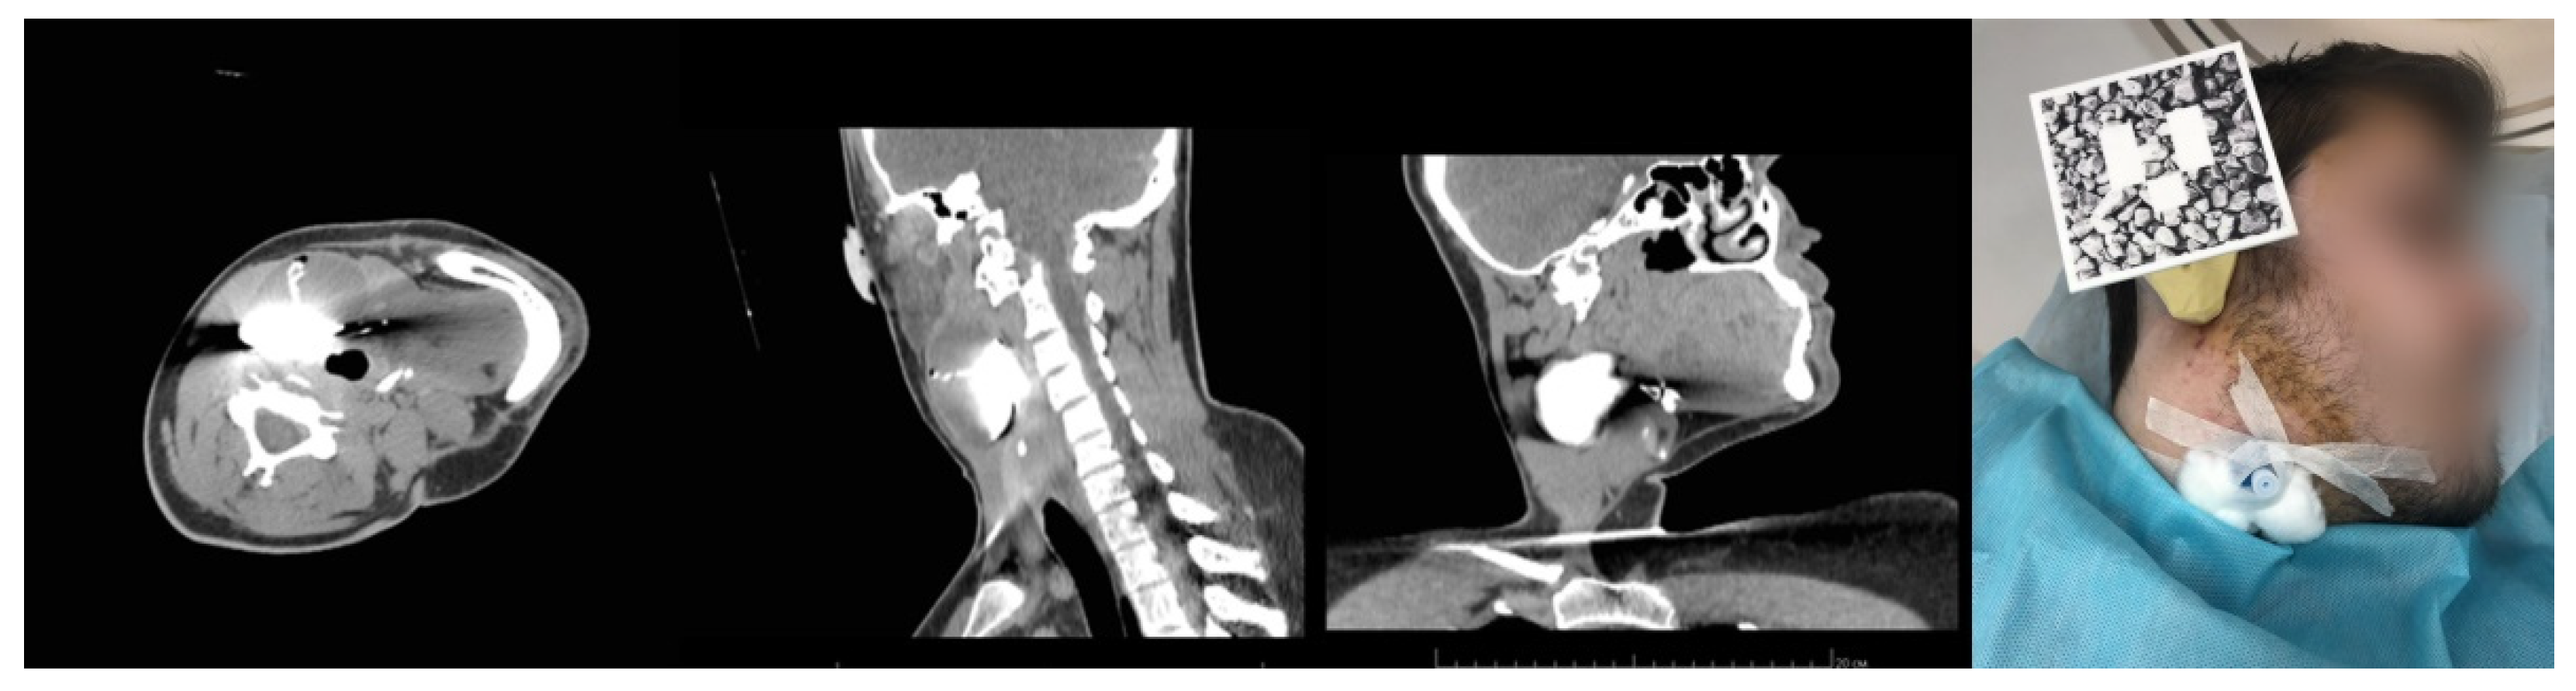

In May of 2021, Patient K., 25 years old, was seeking medical advice in a maxillofacial surgery clinic and was diagnosed with branchial cyst. During inpatient preoperative treatment, the patient underwent MSCT of the neck, with intravenous contrast enhancement and cystography.

The MSCT of the neck was performed in the patient’s selected position, on the back with the head turned all the way to the left (to the healthy side).

Similar to Case 1, Case 3 included a three-step MSCT protocol, with cystography and intravenous contrast enhancement (Figure 9).

The MSCT of the neck in the patient’s selected position, with intravenous contrast enhancement and cystography (left). Venous catheter inserted into the cyst and fixed to the skin, and a PLA splint fixed to a silicon impression of the patient’s ear auricle and auditory passage (right).

Due to the strictly specific lateral positioning of the patient, the use of the navigation frame from Case 2 was impossible.

The developed anatomical navigation splint approach [24] allowed for the attachment of a splint with anatomical landmarks to any of the patient’s body parts by means of an impression compound applied next to the area of interest prior to CT. In this case, the ear was chosen as a relatively immobile body part with a complex structure.

The splint itself consisted of two parts: a reference frame and a fixing handle (Figure 10). The fixing handle had a cross-shaped base firmly installed into the impression compound. It also contained thin metal rods (10 mm × 0.5 mm × 0.5 mm), which served as radiopaque markers, allowing for further calibration of the coordinate systems (similar to the previous case).

The key advantage of this method is the possibility to reference the splint to any part of the patient’s body, as well as its quick installation. However, the chosen body part needs to have a complex anatomical shape and rigid bone structure.